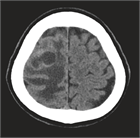

1. 単発・少数転移例では、3 cm以上の大きさの腫瘍に対しては、分割定位放射線照射も行われるが、放射線壊死のリスクも高くなるため、全身状態が安定している患者に対しては手術が第1選択で行われる(推奨度2)。2 cm以上で、症候性でmass effectがあれば手術適応としてもよい。